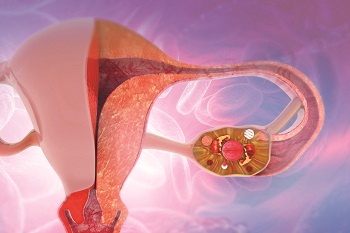

Baixa reserva ovariana e a relação com a infertilidade

Quando o casal apresenta dificuldades para engravidar, a reserva ovariana é um dos primeiros fatores avaliados. Isso porque a sua importância para a fertilidade feminina é enorme, já que representa a quantidade de folículos da mulher. “Os óvulos estão localizados dentro desses folículos, assim, quando o seu número cai, o que chamamos de baixa reserva ovariana, as chances de uma gestação com tratamento podem diminuir consideravelmente”, explica o ginecologista, Marcos Sampaio.

O médico relembra que a reserva ovariana está diretamente relacionada à idade da mulher, e começa a diminuir a partir do nascimento, afetando a quantidade dos óvulos. “A partir dos 35 anos a chance de gravidez começa a diminuir pela piora na qualidade dos óvulos e, quando a mulher chega aos 40, esse estoque de folículos ovarianos fica ainda menor”, ressalta o ginecologista.

A relação entre a baixa reserva ovariana e a infertilidade

O médico destaca que, antes de mais nada, é preciso entender o ciclo menstrual. “A mulher nasce com uma quantidade pré-determinada de folículos ovarianos e, a partir da puberdade, uma parte do seu estoque é utilizado a cada mês”.

Ele lembra que é durante o ciclo menstrual que o corpo se prepara para a gestação. “Entre as suas diversas funções, os hormônios atuam em uma parcela dos folículos ovarianos para que eles cresçam. No entanto, apenas um se desenvolve, liberando o óvulo para ser fecundado. Os folículos que não desenvolveram são naturalmente eliminados. Esse processo se repete a cada ciclo até a chegada da menopausa”, diz.

Além da quantidade, a qualidade dos óvulos também é afetada com o tempo, diminuindo a chance de gravidez e aumentando o risco de abortamento espontâneo e alterações genéticas. Mas, além da idade, outros fatores podem resultar em uma baixa reserva ovariana, como doenças que afetam os ovários, por exemplo. Entre as quais destaca-se a endometriose. “Os tratamentos oncológicos, tabagismo também diminuem a reserva. A falência ovariana prematura (FOP), também é conhecida como menopausa precoce, ocorre quando o funcionamento dos ovários é interrompido antes de a mulher completar 40 anos”, destaca Sampaio.

A avaliação da reserva ovariana é um dos exames solicitados durante a investigação da infertilidade feminina e antes de se iniciar tratamento com reprodução assistida. A partir das informações coletadas, o médico consegue avaliar os níveis da paciente e orientar o casal sobre os próximos passos para engravidar. Ela pode ser feita por três tipos de exames, são eles: a ultrassonografia transvaginal; as dosagens do hormônio folículo-estimulante (FSH) e o hormônio antimülleriano. “A ultrassonografia transvaginal é utilizada para contar o número de folículos antrais da paciente. Quanto maior a quantidade de folículos, maior será a resposta ovariana à estimulação quando houver a necessidade de tratamento. As dosagens hormonais medem os níveis de FSH e estrogênio. Eles atuam diretamente no ciclo menstrual, por isso, o desequilíbrio na produção desses hormônios pode indicar uma baixa reserva ovariana. De forma parecida, medir a produção do hormônio antimülleriano ajuda a estimar quantos óvulos a mulher ainda pode produzir”, explica o ginecologista.

O auxílio da reprodução assistida

As técnicas de reprodução assistida podem ser eficazes mesmo em casos de baixa reserva ovariana, dependendo do nível da paciente. Segundo Sampaio, a técnica mais indicada é a fertilização in vitro (FIV), por ser a mais eficaz e com a maior taxa de sucesso para os casos de infertilidade conjugal. “Ela começa com uma estimulação ovariana para desenvolver mais folículos e aumentar o número de óvulos maduros usados na fecundação. Para isso, a paciente recebe medicamentos hormonais semelhantes aos que são produzidos durante o ciclo menstrual. Quando atingem o tamanho ideal, os folículos são coletados por punção folicular, os óvulos extraídos, selecionados e fecundados em laboratório com os espermatozoides do parceiro. Após alguns dias, os embriões mais saudáveis são transferidos para o útero da paciente”, finaliza o especialista.